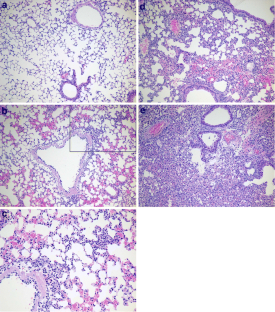

Fig. 1

Fig. 2

Fig. 3

Fig. 4

Fig. 5

Fig. 6

Fig. 7

Fig. 8

Fig. 9

Fig. 10